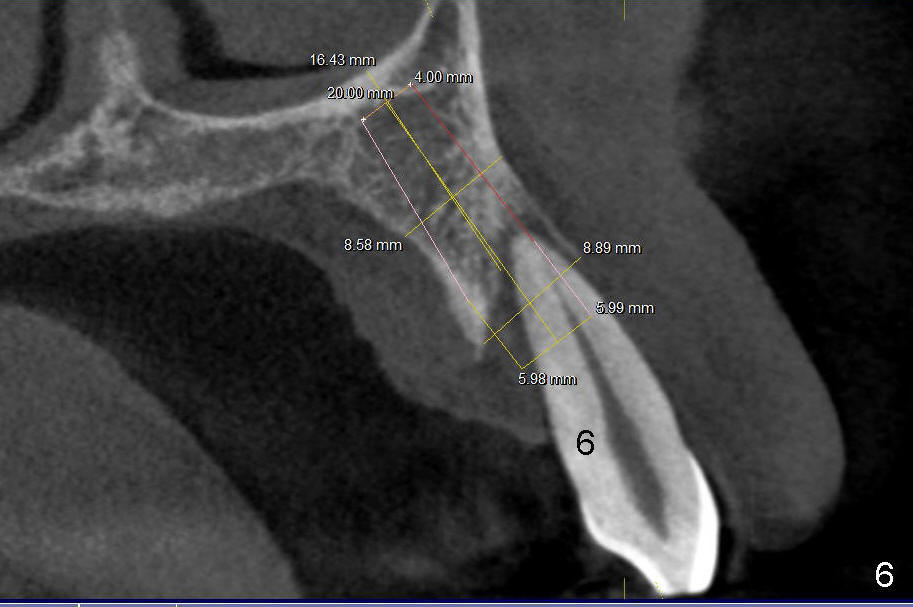

9. Use the teeth #5,7 as guides for #6 pilot drill (Tatum) trajectory, with depth ~14 from gingival margin until the drill is relatively stable

12. Bicon reamers, save bone, later mix with synthetic bone (Osteogen), reamers until 3.0 mm for #7, 3.5 for #6, tap 4.5x20 for 6, then 5x20, possibly 6x20

14. Place implants as palatally as possible. Use Tatum tapered drills if orientation changes unfavorably